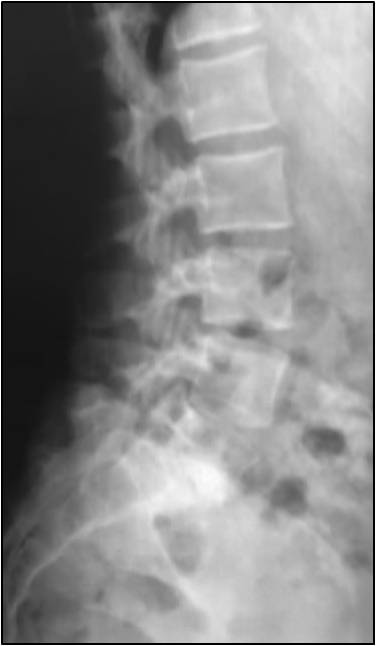

Instabilità lombari dolorose e⁄o evolutive in periodo di crescita. L’ortesi viene indossata per 1 mese e

successivamente la notte e 2 ore dopo la pratica dello sport. Il trattamento si protrae fino alla fine della

crescita (in 2 bilanci clinici successivi l’altezza rimane stabile). Il monitoraggio è ortetico trimestrale,

clinico ed ortetico semestrale, rx ogni anno.